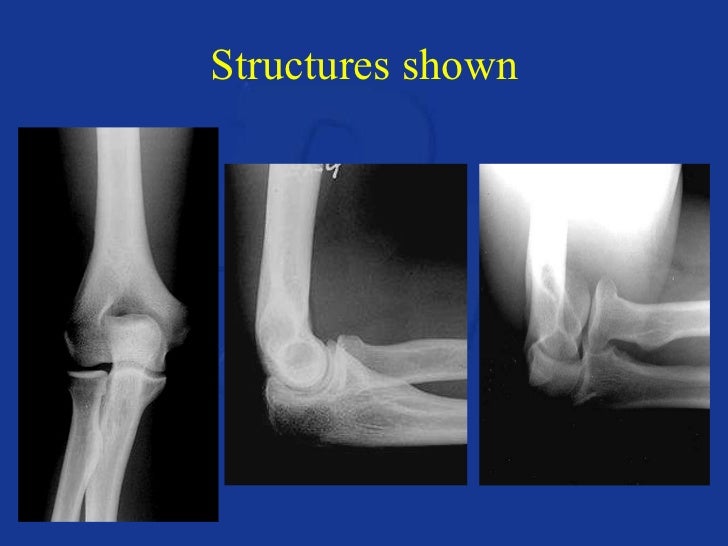

From www.slideserve.com

PPT Radiographic Anatomy and Positioning of the Upper Extremity Upper Extremity X Ray Positioning It is often utilized in the context of trauma to rule. It describes how to perform anteroposterior and. The proximal arm and shoulder. Upper limb radiography is the radiological investigation of the shoulder girdle, humerus, ulna, radius, carpals and metacarpals of the hand. Anatomists divide the bones of the upper limbs, or extremities, into the following main groups: The anatomic. Upper Extremity X Ray Positioning.